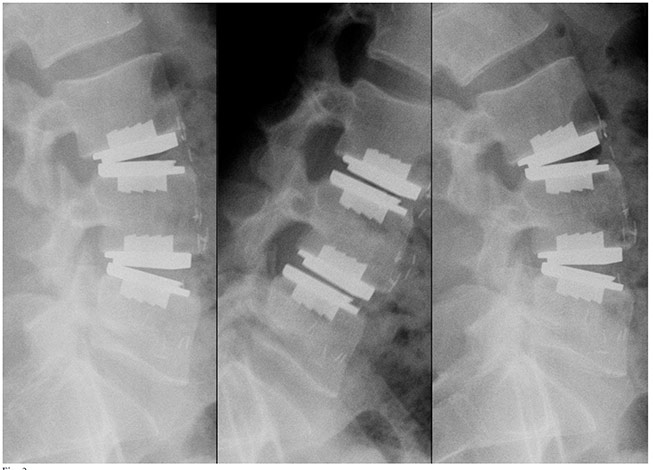

prodisc L Gallery

Click to enlarge image